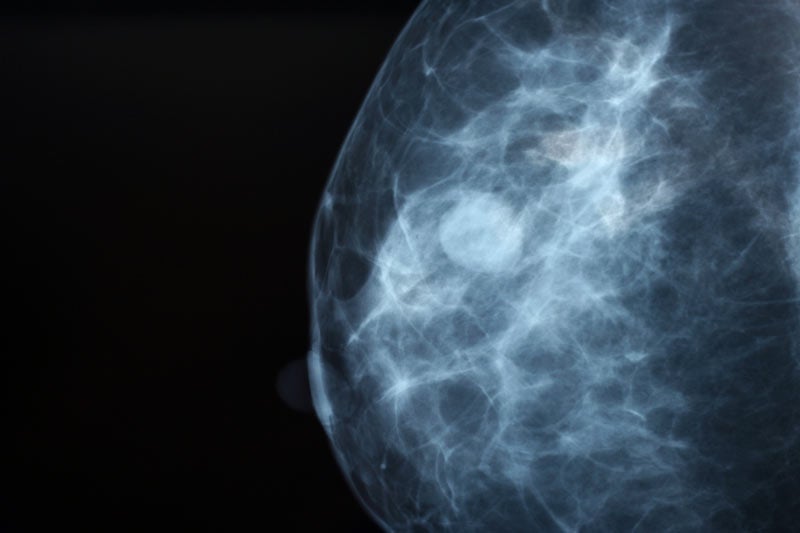

Diagnosis

Early diagnosis through regular screening is key to successful treatment of health conditions related to the breast.